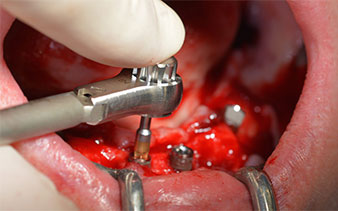

Prima di tutto, è stato individuato il forame mentoniero come limite della struttura anatomica. Successivamente, l'osso corticale della cresta è stato lisciato con un manipolo e una fresa larga a rosetta (Fig. 4).

dentatura residua

Fig. 4

Il protocollo chirurgico per il sistema di implantologia utilizzato (SKY, Bredent medical) prevede una velocità di 1.200 giri/min per la perforazione pilota (Fig. 7 - 9).

Fig. 7

velocità di 1.200 giri/min

Fig. 8

Fig. 9

Questa è la prossima posizione programmata nel sistema Implantmed. Qui è possibile vedere il contrangolo W&H impugnato a un angolo di 45 gradi in posizione medio-caudale, nella zona del 45, al fine di salvaguardare il nervo mentoniero. Il forame mentoniero è un punto di riferimento anatomico per tutte le perforazioni in quest'area. I fori successivi sono realizzati con una velocità ridotta, pari a 300 giri/min (Fig. 10 e 11).

contrangolo W&H

Fig. 10

velocità di 300 giri/min

Fig. 11